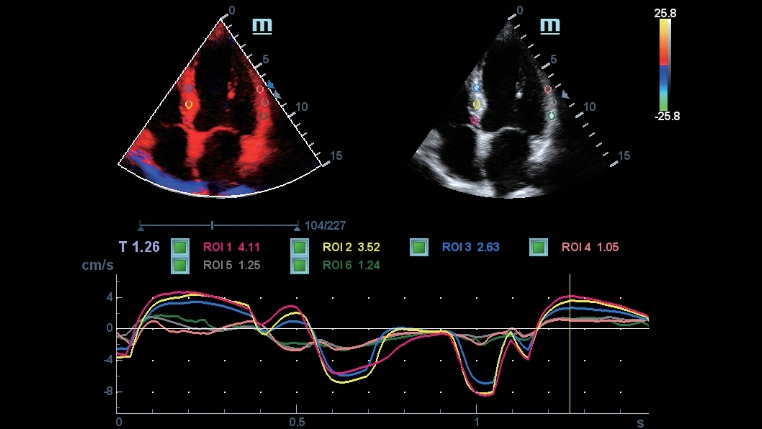

Volledige reeks toepassingshulpmiddelen: nauwkeurigheid met gemak gegarandeerd iTouch

DC-40 met Full HD biedt een reeks hulpmiddelen die diagnostische nauwkeurigheid met gemak maximaliseren. DC-40 met Full HD dekt algemene beeldvorming, OB/GYN en cardiologie en biedt u een complete oplossing voor reguliere klinische toepassingen, met een vereenvoudigde workflow voor effici?ntie.